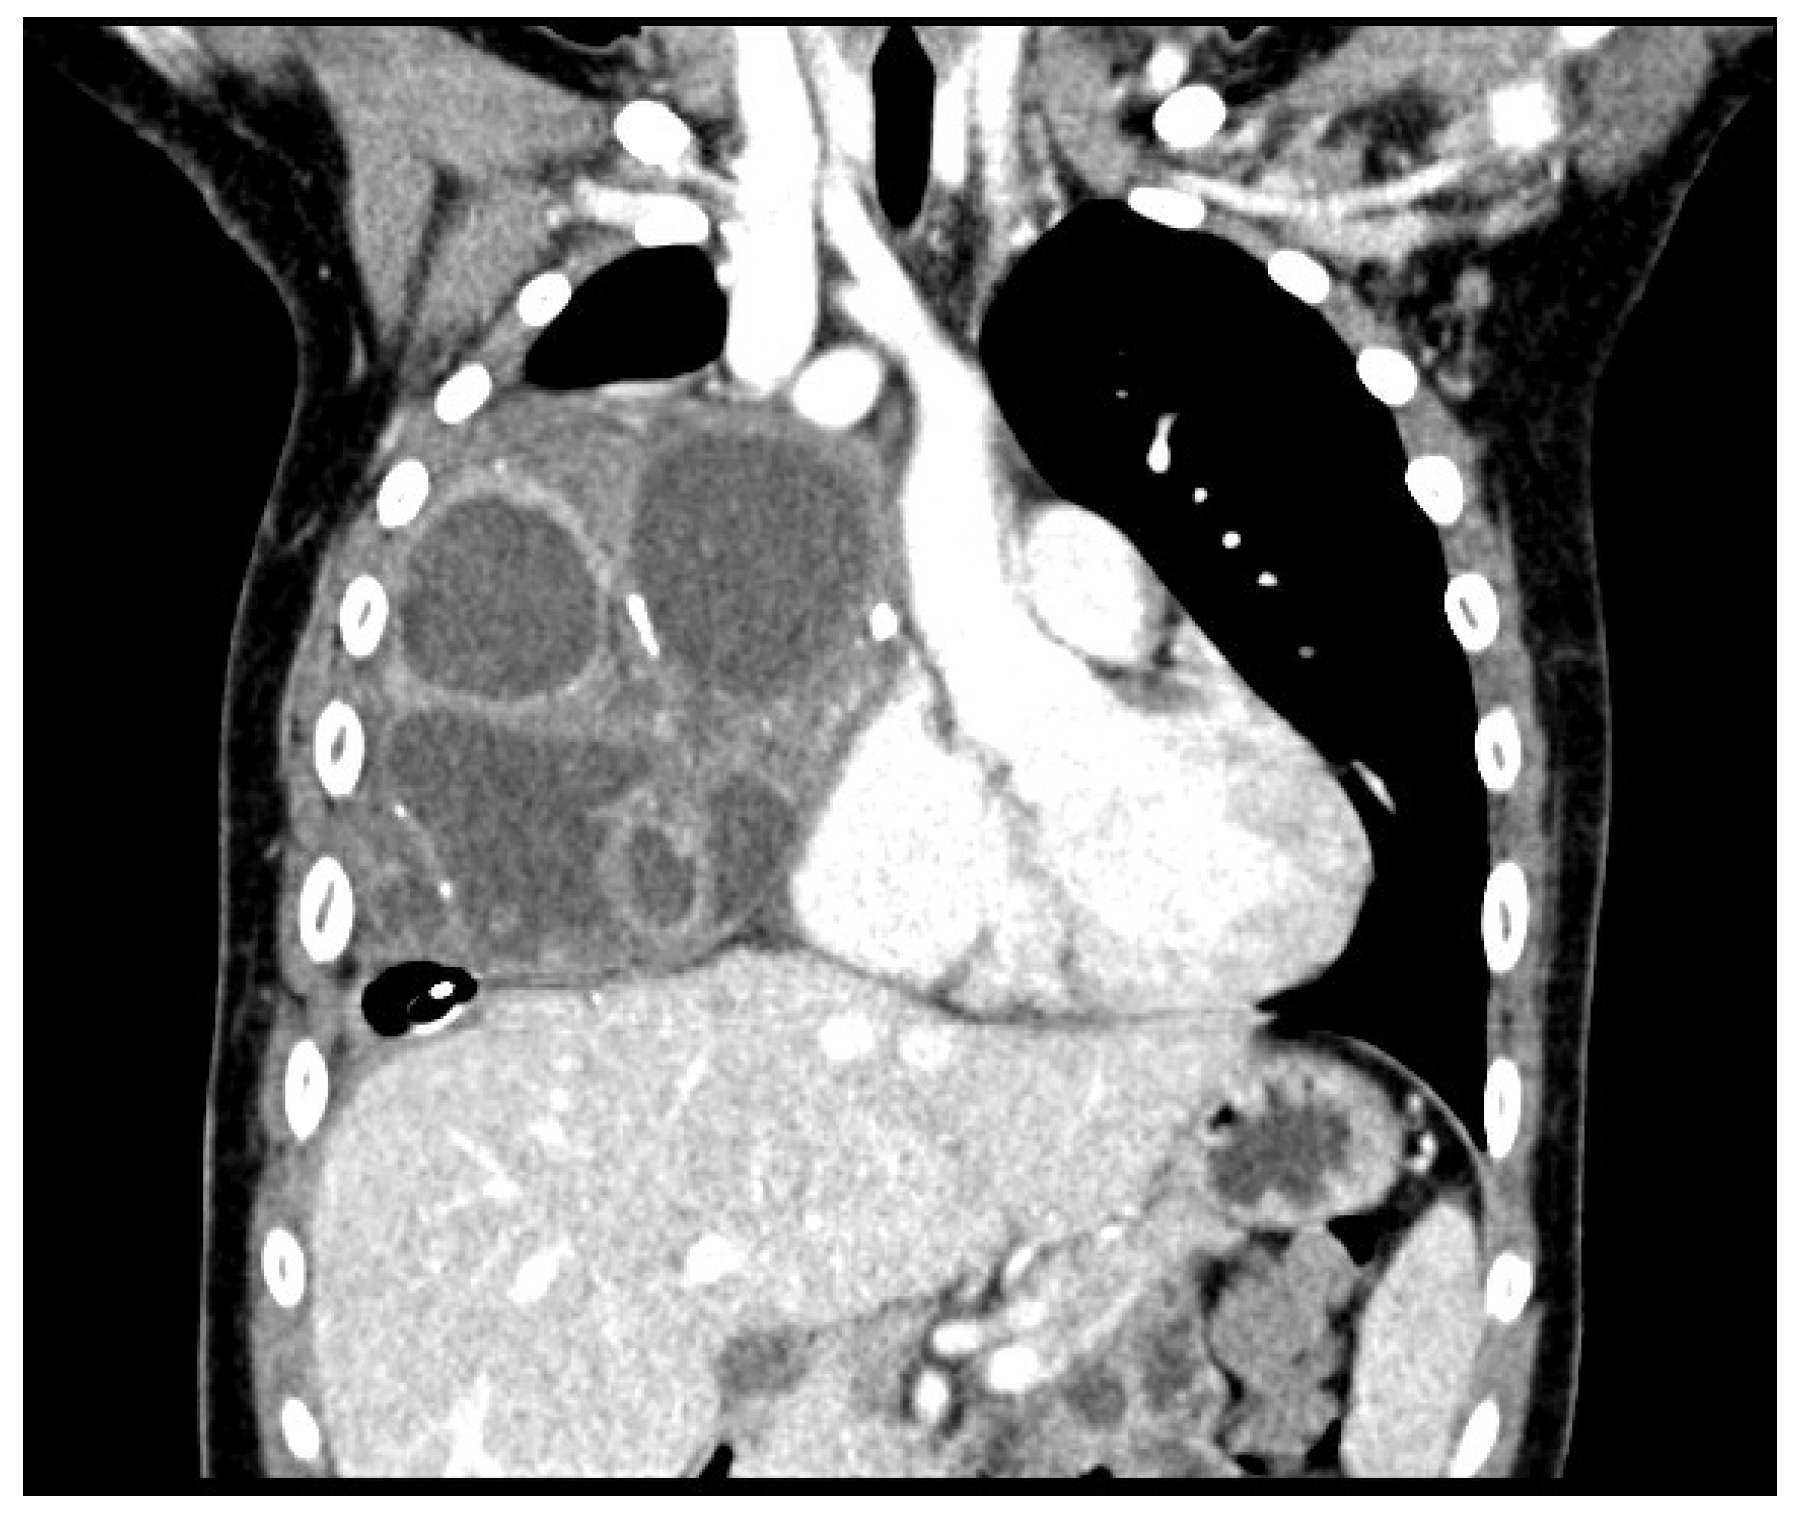

The Key Role of Lung Ultrasound in the Diagnosis of a Mature Cystic Teratoma in a Child with Suspected Difficult to Treat Pneumonia: A Case Report

2. Case Report